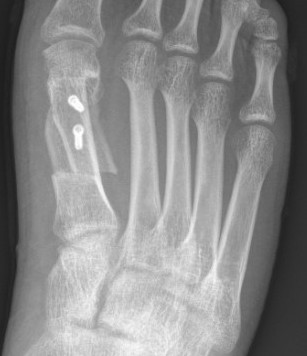

Lapidus Procedure / TMT arthrodesis + DTSP

Indications

- moderate to severe HV

- TMTJ hypermobility

- metatarsus primus varus

Technique

Triplanar correction - coronal / sagittal / rotational

Results

Do et al Orthop Clin North Am 2022

- systematic review of 1800 Lapidus

- complication rate 17%

- hardware pain 3%

- nonunion 3%

- delayed union 2%

- wound complication 1%